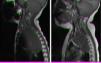

All patients managed with chemotherapy had favourable outcomes (Fig. 1) except one who required laminectomy. All were patients who presented with SCC at onset.

Magnetic resonance imaging (MRI) in patient with neuroblastoma associated with spinal compression at onset. (a) Mass located in the right superior mediastinum measuring 7×5×9cm compressing the spinal cord from the C7-T1 level to the T3-T4 level. (b) MRI following administration of a carboplatin and etoposide cycle: mass measuring 5×5×8cm, with a smaller intracanal component and a reduced mass effect on the spinal cord, which has recovered in terms of both thickness and signal intensity.